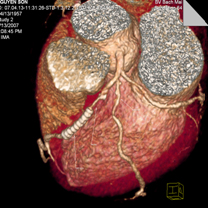

Máy chụp cắt lớp vi tính đa dẫy (MutiSection Computed Tomography- MSCT). Với máy thế hệ mới nhất này, trong một vòng quay của bóng có thể cắt tới 128 lát cắt. MSCT ứng dụng chủ yếu trong thăm khám tim và mạch máu, trong đó có động mạch vành, kiểm tra các bất thường về giải phẫu động mạch vành, các cầu nối mạch vành, thăm dò hoạt động các buồng tim, đánh giá tình trạng vôi hoá động mạch vành, các mạch máu phổi, ngoài ra MSCT giúp đánh giá tình trạng tưới máu cơ tim trong bệnh thiếu máu cơ tim cục bộ. MSCT còn đánh giá bệnh lý động mạch như phình, bóc tách động mạch chủ, động mạch đùi, động mạch chậu rất chính xác. Kiểm tra sau phẫu thuật, sau đặt Stent động mạch cũng nhờ vào MSCT.

Hình hẹp động mạch vành trên MSCT